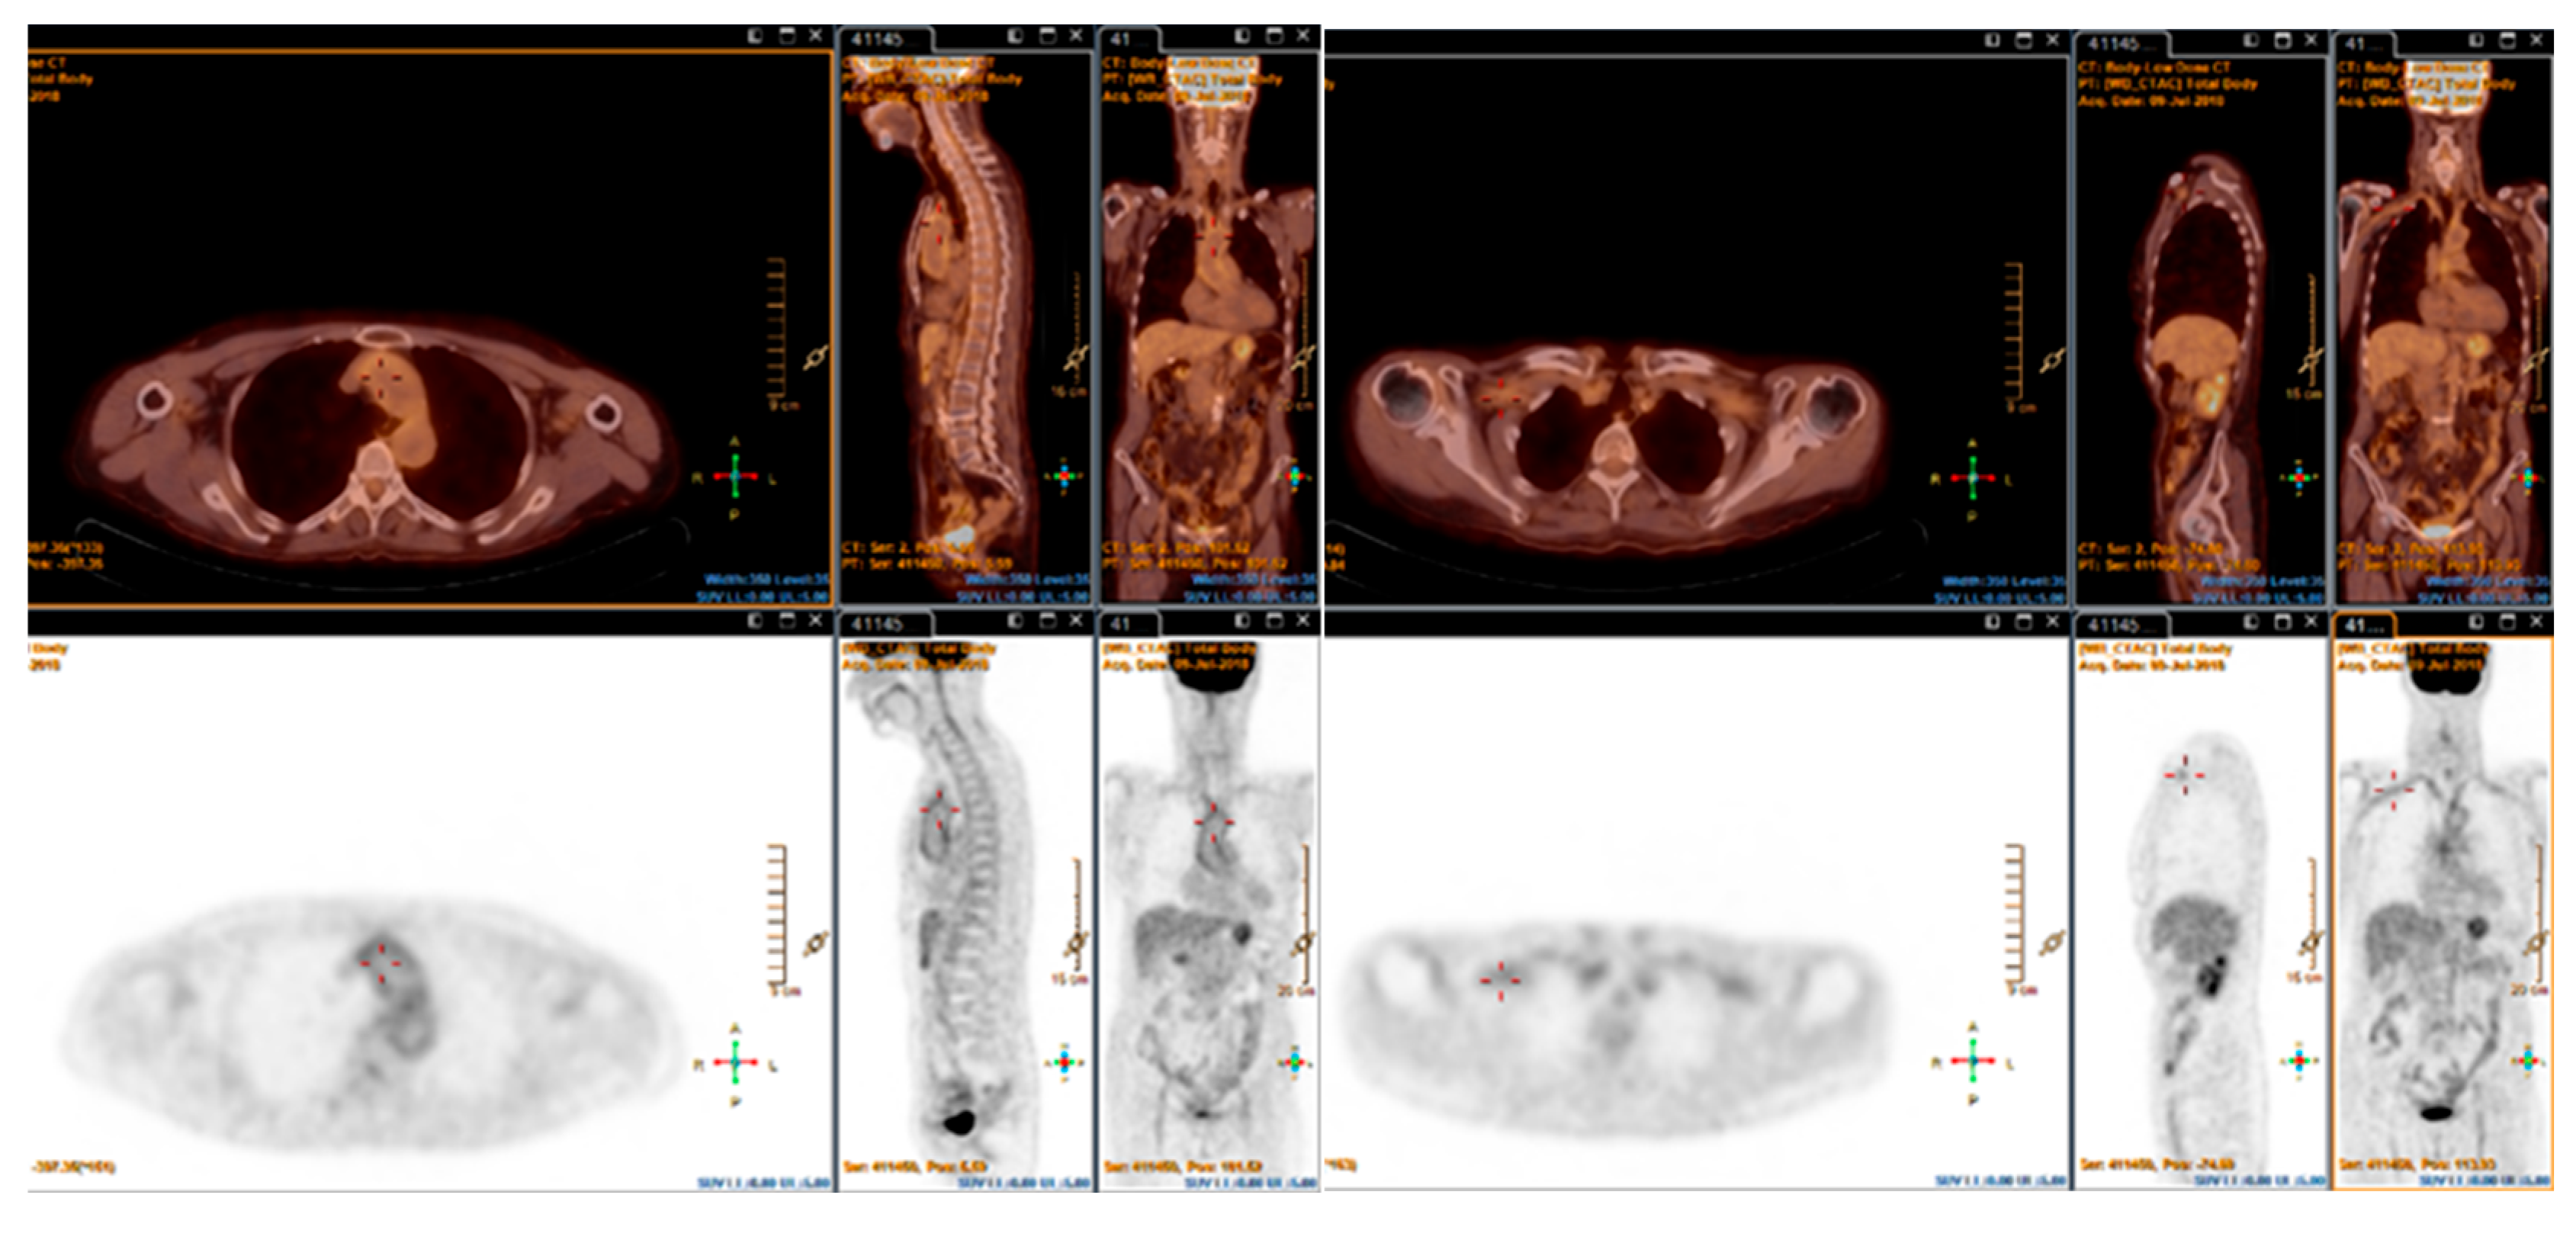

4. Fluorine-18-Fluorodeoxyglucose PET (FDG-PET)

4.1. Giant Cell Arteritis

4.2. Takayasu Arteritis

- Galli, E.; Muratore, F.; Mancuso, P.; Boiardi, L.; Marvisi, C.; Besutti, G.; Spaggiari, L.; Casali, M.; Versari, A.; Rossi, P.G.; et al. The role of PET/CT in disease activity assessment in patients with large vessel vasculitis. Rheumatol. Oxf. Engl. 2022, 61, 4809–4816. [Google Scholar] [CrossRef]

- van der Geest, K.S.M.; Treglia, G.; Glaudemans, A.W.J.M.; Brouwer, E.; Sandovici, M.; Jamar, F.; Gheysens, O.; A Slart, R.H.J. Diagnostic value of [18F]FDG-PET/CT for treatment monitoring in large vessel vasculitis: A systematic review and meta-analysis. Eur. J. Nucl. Med. Mol. Imaging 2021, 48, 3886–3902. [Google Scholar] [CrossRef] [PubMed]

- Grayson, P.C.; Alehashemi, S.; Bs, A.A.B.; Civelek, A.C.; Cupps, T.R.; Kaplan, M.J.; Malayeri, A.A.; Merkel, P.A.; Novakovich, E.; Bluemke, D.A.; et al. 18F-Fluorodeoxyglucose-Positron Emission Tomography as an Imaging Biomarker in a Prospective, Longitudinal Cohort of Patients with Large Vessel Vasculitis. Arthritis Rheumatol. 2018, 70, 439–449. [Google Scholar] [CrossRef] [PubMed]

- Marvisi, C.; Bolek, E.C.; Ahlman, M.A.; Alessi, H.; Redmond, C.; Muratore, F.; Galli, E.; Ricordi, C.; Kaymaz-Tahra, S.; Ozguven, S.; et al. Development of the Takayasu Arteritis Integrated Disease Activity Index. Arthritis Care Res. 2024, 76, 531–540. [Google Scholar] [CrossRef] [PubMed]

- Lee, K.H.; Cho, A.; Choi, Y.J.; Lee, S.; Ha, Y.; Jung, S.; Park, M.; Lee, J.; Lee, S.; Park, Y. The role of 18F-fluorodeoxyglucose-positron emission tomography in the assessment of disease activity in patients with takayasu arteritis. Arthritis Rheum. 2012, 64, 866–875. [Google Scholar] [CrossRef] [PubMed]

- Kang, F.; Han, Q.; Zhou, X.; Zheng, Z.; Wang, S.; Ma, W.; Zhang, K.; Quan, Z.; Yang, W.; Wang, J.; et al. Performance of the PET vascular activity score (PETVAS) for qualitative and quantitative assessment of inflammatory activity in Takayasu’s arteritis patients. Eur. J. Nucl. Med. Mol. Imaging 2020, 47, 3107–3117. [Google Scholar] [CrossRef]

- Zhang, X.; Zhou, J.; Sun, Y.; Shi, H.; Ji, Z.; Jiang, L. 18F-FDG-PET/CT: An accurate method to assess the activity of Takayasu’s arteritis. Clin. Rheumatol. 2018, 37, 1927–1935. [Google Scholar] [CrossRef]

- Kobayashi, Y.; Ishii, K.; Oda, K.; Nariai, T.; Tanaka, Y.; Ishiwata, K.; Numano, F. Aortic wall inflammation due to Takayasu arteritis imaged with 18F-FDG PET coregistered with enhanced CT. J. Nucl. Med. Off. Publ. Soc. Nucl. Med. 2005, 46, 917–922. [Google Scholar]

- Tezuka, D.; Haraguchi, G.; Ishihara, T.; Ohigashi, H.; Inagaki, H.; Suzuki, J.-I.; Hirao, K.; Isobe, M. Role of FDG PET-CT in Takayasu arteritis: Sensitive detection of recurrences. JACC Cardiovasc. Imaging 2012, 5, 422–429. [Google Scholar] [CrossRef]